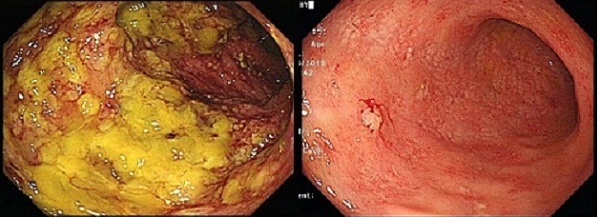

25일 대전성모병원에 따르면 강 교수팀은 최근 심한 복통 및 설사, 발열, 식욕 부진 등의 증상으로 입원한 51세 A환자에게 대변 검사와 대장내시경을 실시한 결과 대장염의 원인균인 클로스트리디움 디피실(Clostridium Difficile)을 확인하고 중증의 위막성 대장염을 진단했다.

이후 위막성 장염의 치료제인 반코마이신을 투여했으나 호전이 없자 지난달 29일 대변 세균총 이식을 시행, 성공적인 임상 결과를 얻었다.

대변 세균총 이식은 건강한 사람의 대변에서 추출한 미생물을 환자의 장에 투입해 환자의 장내 미생물의 균형을 맞추는 시술로서 치료 효과는 물론 성공률이 70-90%로 높고 재발률이 낮은 게 장점이다. 주로 여러 번 재발하거나 항생제에 반응이 없는 위막성 대장염 환자가 대변 세균총 이식 대상이 된다.